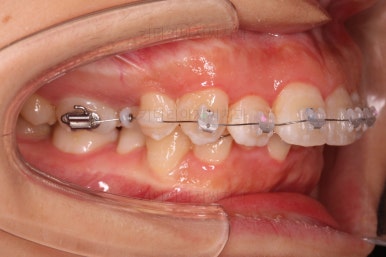

장치를 부착합니다.

이번 환자분이 선택한 장치는 엠파워 클리어라고 하는 자가결찰 세라믹 장치인데요.

철사를 묶는(결찰) cap이 장치에(자가) 달려있는 장치 중에 세라믹 성분으로 되어 심미성이 우수한 브라켓입니다.

대표적으로는 클리피씨 장치 등이 있습니다.

우선은 적응을 위해서 윗니만 장치를 부착하고요.

아랫니는 과개교합 개선을 위해 앞니 먼저 시작합니다.